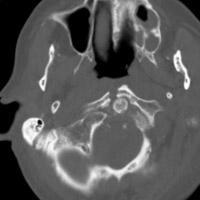

- Click on the image for a larger versionCAxial CT. The image shows the fracture of the posterior arch of C1.